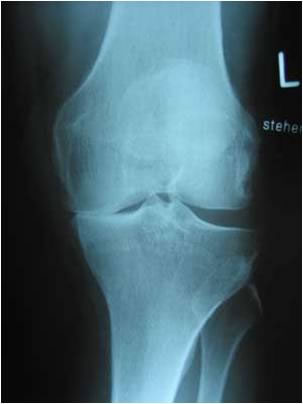

Arthrosetherapie

Arthrose ist eine fortschreitende Abnutzungserscheinung des Gelenkknorpels und der angrenzenden Knochenstrukturen. Die Folge sind Schmerzen, Bewegungseinschränkungen und zunehmende Deformitäten der betroffenen Gelenke. Die Lebensqualität des Patienten wird in allen Lebensbereichen zum Teil erheblich beeinträchtigt.

Zur konservativen Behandlung der Arthrose insbesondere der großen Gelenke (z.B. Kniegelenk, Hüftgelenk) und damit zur Verbesserung der Gelenkfunktion, zur Reduktion des Schmerzmittelbedarfs und zur Vermeidung frühzeitiger operativer Eingriffe kann ein Gelenkflüssigkeitsersatz Hyalronsäure verabreicht werden. Die Hauptaufgabe dieser Substanz besteht in der Regulation von Schmierung und Gleitfähigkeit im Gelenk.

Hyaloronsäure unterstützt somit die Stoßdämpferfunktion des Knorpels und wirkt in vielen Fällen lang anhaltend. Außerdem verleiht die Hyaloronsäure der Gelenkflüssigkeit schmerzunterdrückende sowie entzündungshemmende Eigenschaften.

In der Regel werden 3-5 Injektionen Hyaloronsäure im Abstand von je einer Woche in das entsprechende erkrankte Gelenk eingebracht. Die positive Wirkung kann bis zu 6 Monaten oder länger anhalten.